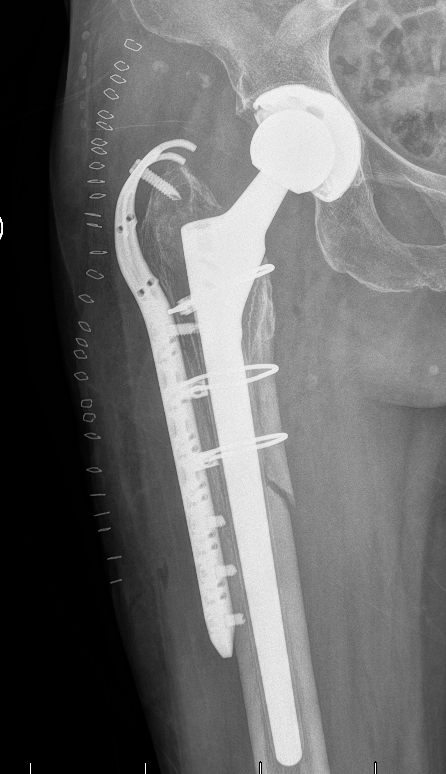

杨小海主任团队为患者实施髋关节翻修术

杨小海主任表示,假体周围骨折翻修具有相当大的难度,既要处理失效假体,又要最大限度保证术后内固定和假体的稳定,还要保证关节不会脱位,兼顾术后康复锻炼。此类手术需同时解决骨折复位、假体稳定性重建和骨缺损修复三大难题。得益于苏大附四院骨科近年来在髋关节外科领域积累的丰富经验,手术非常成功,为患者未来的生活质量提供了保障。